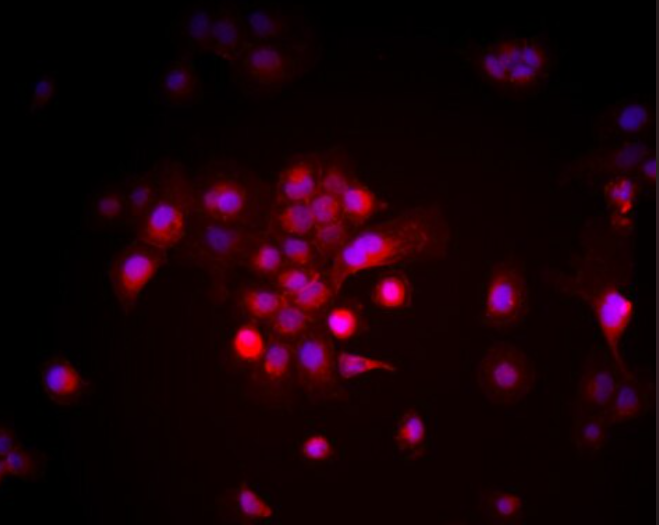

贴壁生长,呈梭形或纤维母细胞样

人乳腺癌细胞MDA-MB-436来源于乳腺癌患者胸腔积液转移灶,是一种经典的三阴性乳腺癌(TNBC)细胞系。其分子特征为ER、PR和HER2均为阴性,同时携带BRCA1和TP53突变。MDA-MB-436细胞具备纤维母细胞样形态,表现为高度侵袭性和迁移能力。由于其BRCA1突变背景,该细胞常用于研究DNA修复通路及PARP抑制剂敏感性,在TNBC的基础研究和新药开发中有着重要应用价值。

2. **DNA损伤检测**:利用γ-H2AX免疫荧光或Western Blot检测药物处理后的DNA损伤水平。